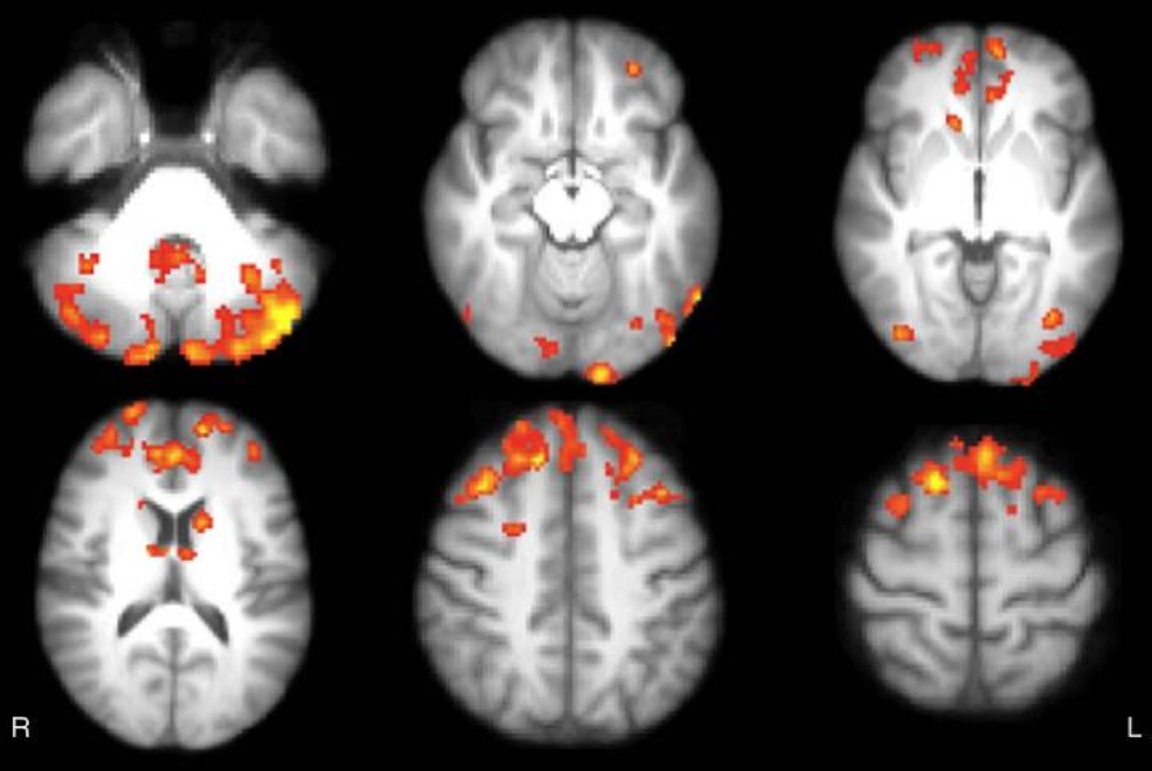

Mapas estadísticos axiales muestran las áreas de reducción de la conectividad funcional en el tálamo de pacientes con EM, en comparación los sujetos sanos. Los pacientes mostraron significativamente menor conectividad funcional en cerebelo, cortezas frontal y occipital, núcleo caudado ytálamo, de forma bilateral. Fuente: Radiological Society of North America.

Tras el seguimiento realizado a los 12 pacientes que jugaron a videojuegos se constató en estos un aumento significativo de la conectividad funcional del tálamo, en áreas del cerebro que constituyen una de las redes cerebrales más importantes para la cognición. Estos resultados, afirman los investigadores, proporcionan un ejemplo de la plasticidad del cerebro, que es la capacidad que este órgano tiene para formar nuevas conexiones a lo largo de la vida.

Las modificaciones en la conectividad funcional que se mostraron tras el entrenamiento con videojuegos se correspondieron con mejoras significativas en puntuaciones de pruebas que evaluaban la atención sostenida y la función ejecutiva, que son habilidades cognitivas de nivel superior que nos ayudan a organizar nuestras vidas y a regular nuestro comportamiento.